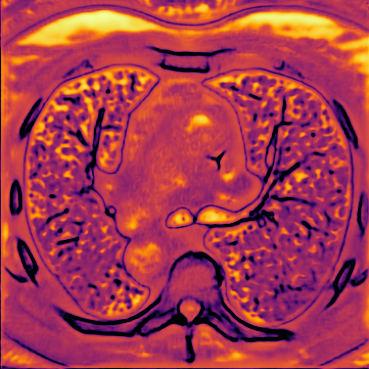

Figure 5 shows an example of a spatio-temporal regularization parameter-map which was estimated using the proposed approach for an acceleration factor of . The network estimates the regularization parameter-map to be pointwise relatively consistenly higher than the spatially required regularization. This result is in fact expected as the temporal dimension is the one for which the gradients of the images are the sparsest because of the high temporal correlation. Further, we see how the network consistently predicts both the spatial regularization as well as the temporal regularization to be less strong in the area where most of the movement is expected, i.e. in the cardiac region.